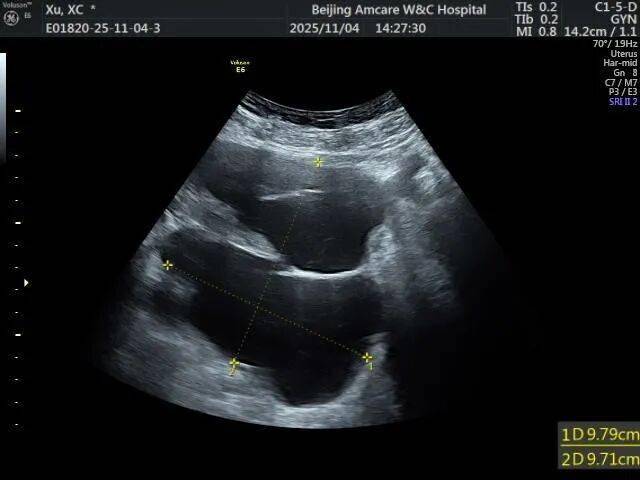

1. 超声检查:首选且最常用的检查。B超下可见盆腔内囊性无回声区,边界多不清晰,形态不规则,囊壁薄而模糊,内部无血流信号,结合患者有手术史或盆腔炎病史,可初步诊断。

2. 影像学进一步检查:若超声无法明确,可做盆腔CT或MRI。CT/MRI能更清晰地显示假囊的位置、大小、与周围器官的关系,排除恶性病变(如卵巢癌、转移性肿瘤等)。